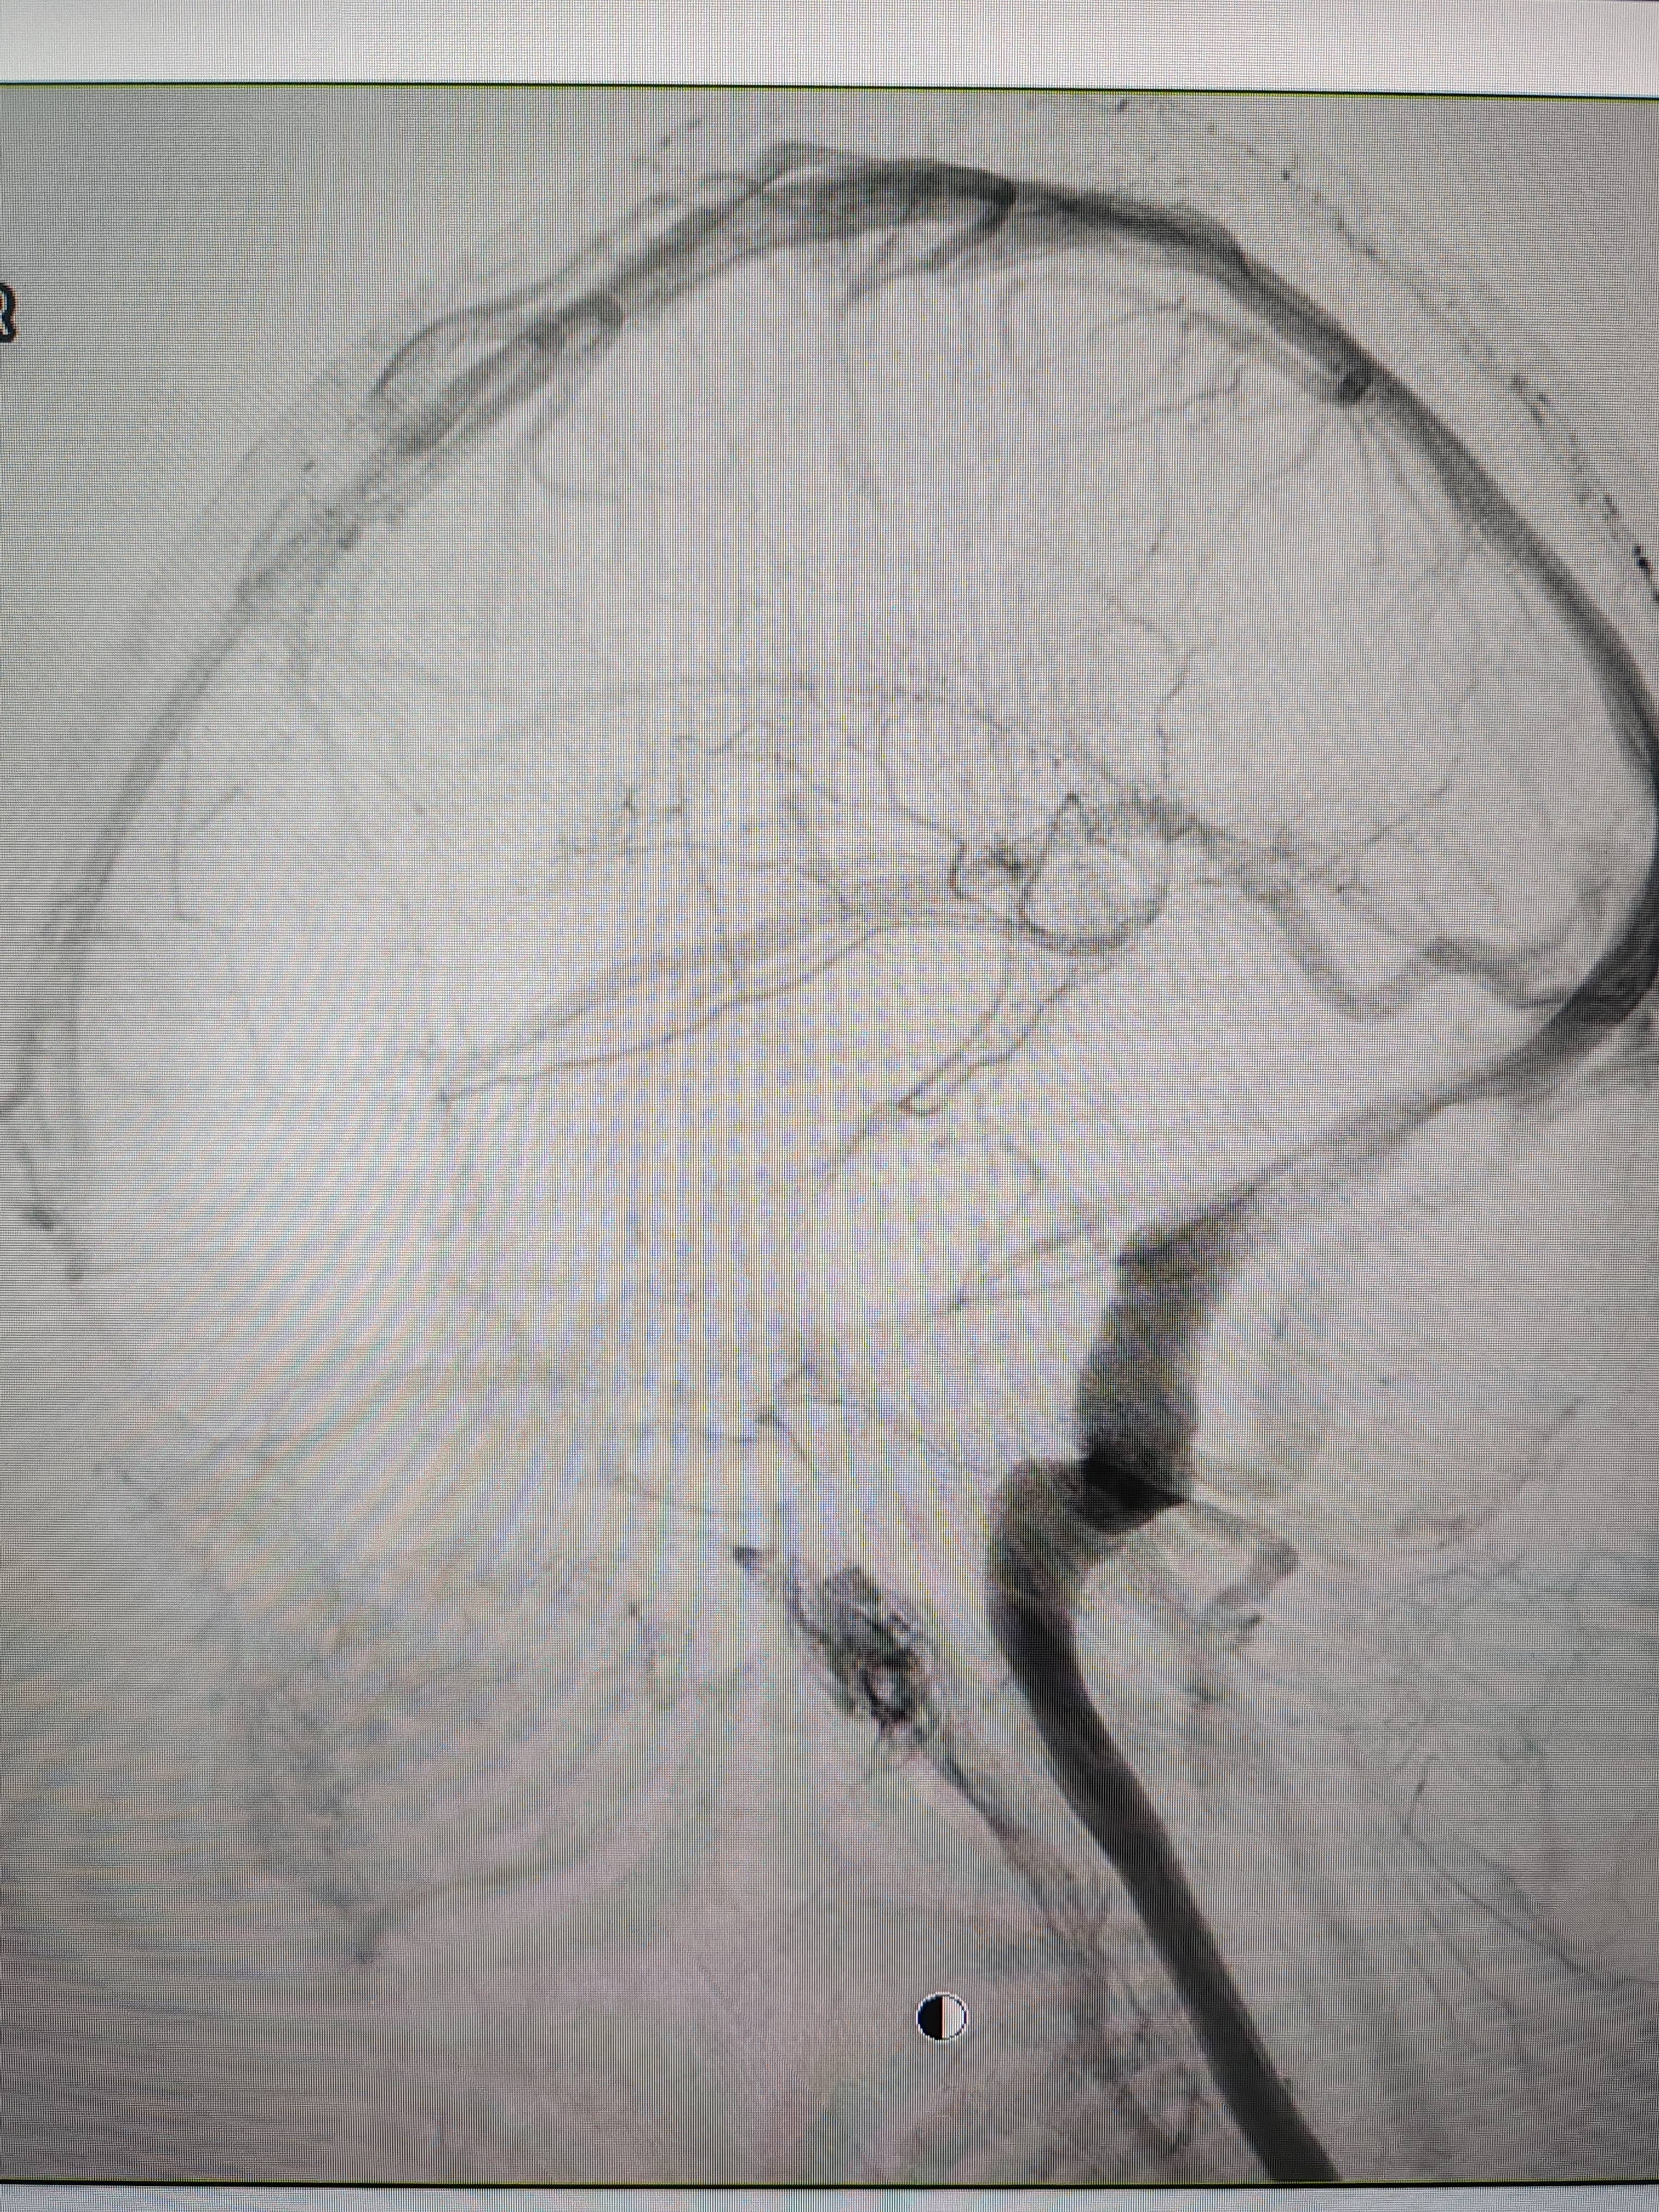

患者造影图像显示,其耳侧静脉窦狭窄truechain币行情。 南方+ 欧阳少伟 拍摄

李宝民举例说,通过查体、CT、造影等影像技术的检查,患者赵女士是由于静脉窦狭窄,导致缓慢的静脉血流也出现“湍流”现象,其拐弯、打漩涡、回流产生的声响,又顺着骨传导,传至耳蜗处,进而让患者出现搏动性耳鸣的症状truechain币行情。